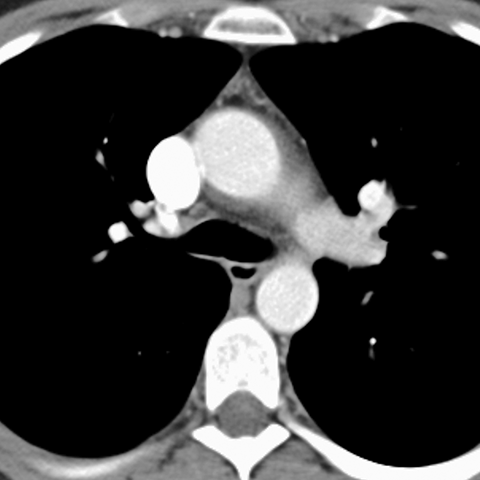

Normal Thymus, 22 Year Old (Chest CT) [3 of 3]